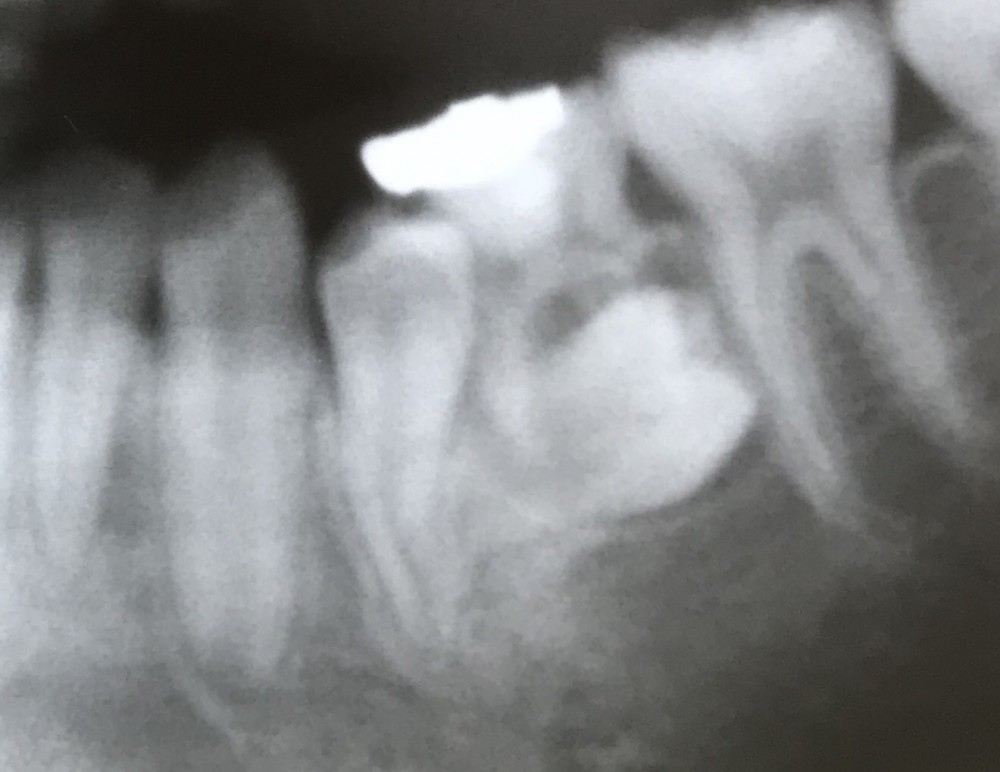

初診時13才0ヶ月、主訴は左下歯茎の腫れ。

下の写真は初診時のものです。